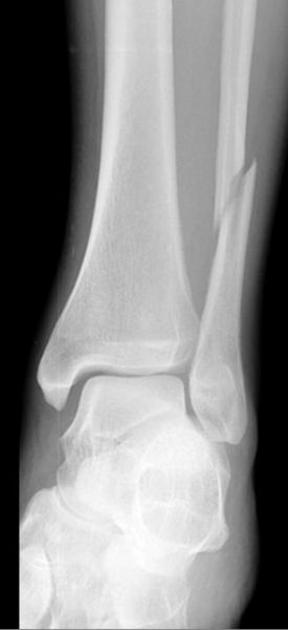

(Справа) MPT PDBИ, режим подавления сигнала от жира, аксиальный срез: у этого же пациента определяется разрыв передней и задней синдесмовидных связок ПБМС. Малоберцовая кость смещается латеральнее своего нормального положения. (Слева) Рентгенография в передне-задней проекции: определяется поперечный перелом головки малоберцовой кости с отсутствием смещения. Другие патологические изменения не определяются. Эти признаки свидетельствуют о варусной деформации и должны повысить подозрение по поводу несостоятельности малоберцовой коллатеральной связки.

2. Рентгенография при переломе проксимального большеберцово-малоберцового сустава и проксимального отдела малоберцовой кости:

• Перелом:

о Светлая линия перелома в головке, шейке или проксимальном диафизе малоберцовой кости:

- Простой или оскольчатый

- ± сопутствующий перелом латеральной верхней суставной поверхности большеберцовой кости

- ± травма Мезоннева лодыжки

• Вывих:

о Нормальная анатомия:

- Передне-задняя проекция: головка малоберцовой кости находится выше латерального кортикального слоя большеберцовой кости

- Латеральная проекция: только часть головки малоберцовой кости выступает через задний кортикальный слой большеберцовой кости

о Переднебоковой вывих:

- Передне-задняя проекция: головка малоберцовой кости визуализируется с минимальным перекрытием большеберцовой кости или его отсутствием

- Боковая проекция: головка малоберцовой кости смещается кпереди, находясь полностью выше большеберцовой кости

о Заднемедиальный вывих:

- Передне-задняя проекция: головка малоберцовой кости находится за большеберцовой костью

- Боковая проекция: головка малоберцовой кости выступает кзади от большеберцовой кости

о Верхний вывих:

- Верхний вывих головки малоберцовой кости при котором шиловидный отросток находится на уровне коленного сустава